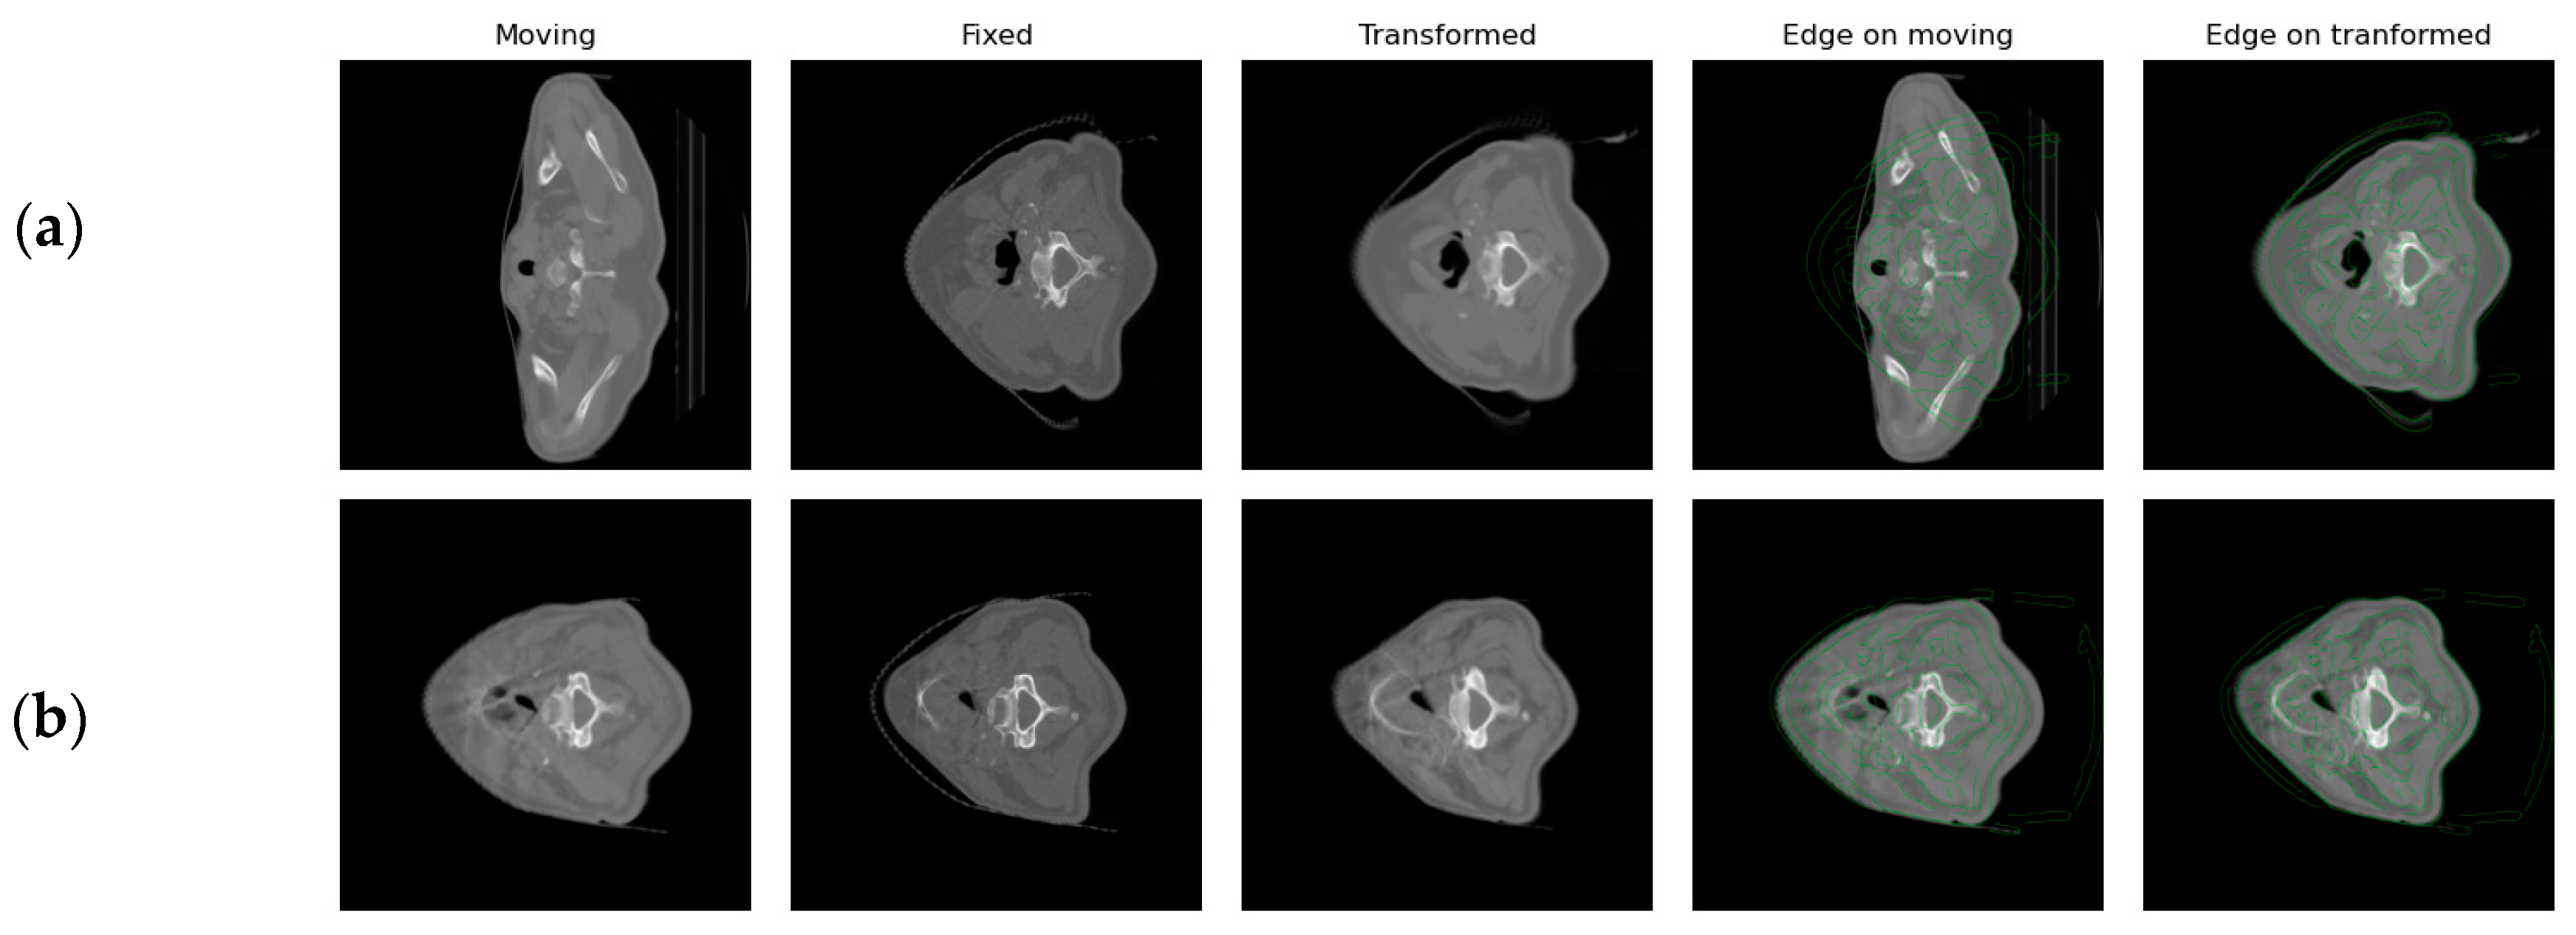

3.4. Segmentation Qualitative Comparison Analysis

Segmentation examples of the proposed AttentionUNet network and the different comparison models are presented in Figure 4a for the public dataset and in Figure 4b for the private dataset. Regarding the public dataset, the AttentionUNet-based models achieved visually better results in comparison with the other DL models that produced slightly rotated masks in the same gland. As such, the proposed framework generated a smoother region and suppressed a fraction of the over-segmented regions of the other networks. By contrast, UNet, SwinUNETR, and SegResNet have over-segmented a small part of the parotid gland on the left and concurrently have produced fewer smooth masks. In a similar manner, SwinUNETR presented a larger difference in the parotid gland when compared with the ground truth.

Concerning the utilization of the private dataset as an external validation, it can be observed that the proposed AttentionUNet model best approximates the ground truth as it reduces over-segmentation, while also producing smoother segmentations. In comparison, UNet failed to outline a large portion of the parotid gland, whereas the other models produced slightly different structures on the left and under-segmented the right parotid. In this example, although AttentionUNet did not capture the whole structure on the right, it reduced false positives and produced very accurate results on the left one.

Figure 4. Segmentation results of the tested models on (a) the public dataset; (b) the private dataset. Each column represents different algorithmic designs. The segmentation masks of the parotid glands are displayed in red.